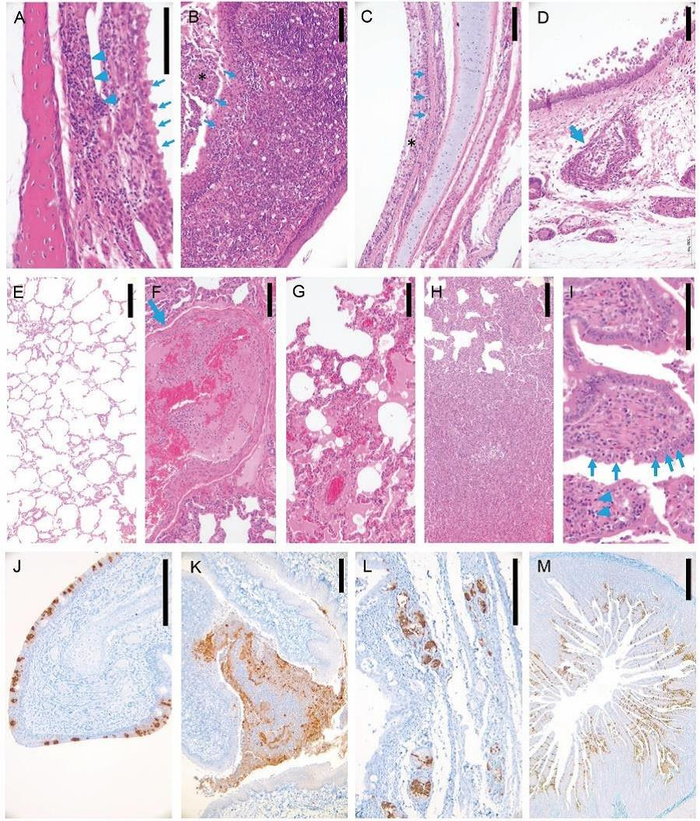

新冠病毒在感染猫呼吸系统及消化系统高效复制,引起病理损伤和炎症反应,病毒感染后3天病死或安乐死猫组织病理学及免疫组化研究。(A)鼻粘膜上皮排列紊乱,纤毛脱落(箭头),固有层淋巴细胞侵润(箭头)。(B)扁桃体上皮细胞变性、坏死,粘膜上皮(星号)表面覆盖细胞碎片及中性粒细胞(箭)。(C)气管粘膜上皮变性、坏死(箭),表面覆盖混有大量细胞碎片的黏液(星号)。(D)气管黏液腺上皮坏死,淋巴细胞侵润(箭)。(E)未感染病毒猫肺正常组织结构。(F)肺血管内炎症细胞聚集,纤维蛋白凝结形成(箭)。(G)肺泡内即肺泡间隔大量巨噬细胞及淋巴细胞侵润。(H)肺泡及肺泡间隔炎性侵润和增生。(I)小肠上皮部分细胞变性、坏死,固有层中等程度淋巴细胞侵润(箭)。(J)鼻甲粘膜上皮细胞大量病毒抗原阳性(棕色)。(K)扁桃体粘膜上皮及粘膜表面脱落细胞大量病毒抗原阳性(棕色)。(L)气管黏液腺浆液细胞大量病毒抗原阳性(棕色)。(M)小肠粘膜上皮细胞大量病毒抗原阳性(棕色)。标尺线 A, I = 100 μm, B-H, J-L = 200 μm, M = 500 μm

研究团队还在幼猫(70-100天)中重复了上述在亚成年猫中的复制和传播研究。对接种病毒后于第3天死亡或安乐死的幼猫样本进行的组织病理学研究显示,这两只猫的鼻腔和气管黏膜上皮以及肺部均有大量损伤。